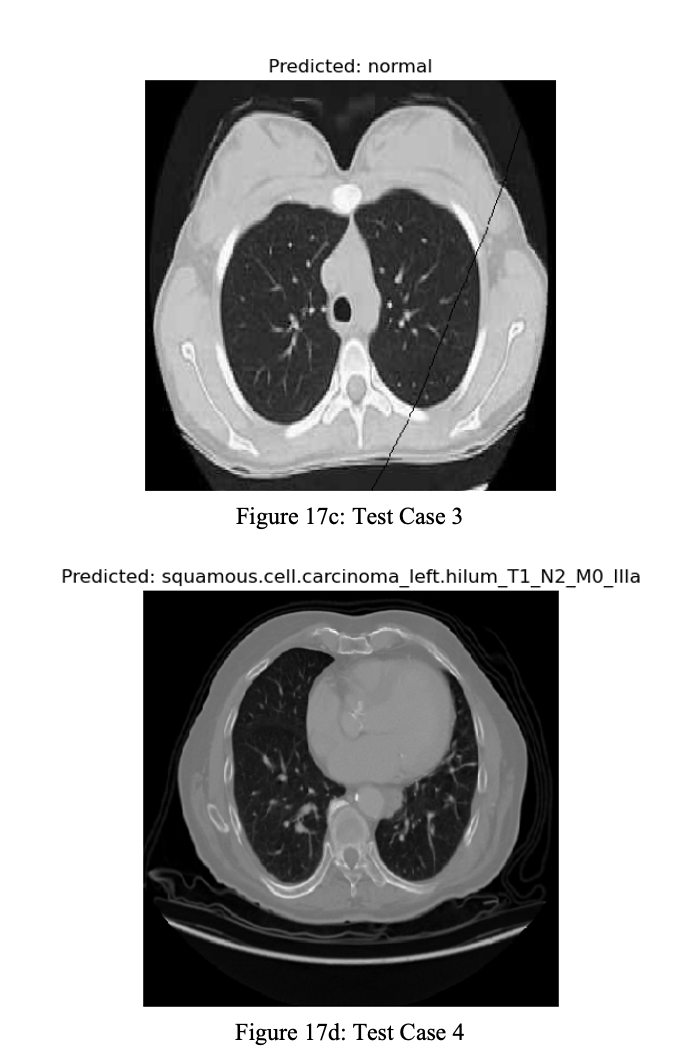

The model was used to make predictions on the Chest CT Scans dataset and the IQ-OTH/NCCD dataset. In (Figure 17a to Figure 17d), the model takes different samples belonging to each class of the Chest CT Scans dataset and predicts which class the Chest CT scan image belongs to.